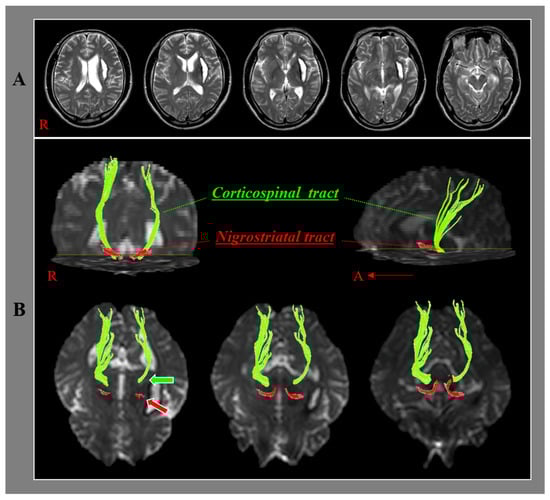

Relationship of the Nigrostriatal Tract with the Motor Function and the Corticospinal Tract in Chronic Hemiparetic Stroke Patients: A Diffusion Tensor Imaging Study

- Yeo, S.S.; Seo, J.P. The nigrostriatal tract between the substantia nigra and striatum in the human brain: A diffusion tensor tractography study. J. Korean Phys. Ther. 2020, 32, 388–390. [Google Scholar] [CrossRef]